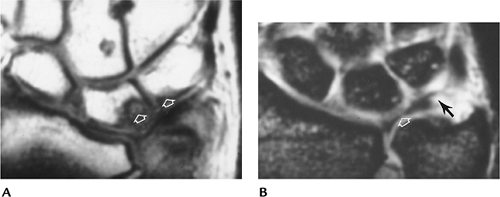

FIGURE 9-56 MR images in patients with ulnar lunate abutment syndrome. (A) T1-weighted image shows low signal intensity in the lunate and adjacent triquetrum. (B) Gradient echo coronal shows displacement of the radial aspect of the triangular fibrocartilage (open arrow) and a peripheral tear (black arrow).